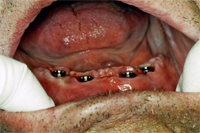

Am 2. Oktober 2006 wurden unter Aufklappung vier Implantate gesetzt. Eine Woche später kommt der Patient zur Nahtentfernung (Abb. 1). Die postoperative Schwellung ist verschwunden und die Nähte werden entfernt. Die Einheilkappen sind für die Abdrucknahme vom Implantat entfernt (Abb. 2). Mit der bestehenden Prothese wird nun der Abdruck genommen. Noch gleichentags fertigt der Techniker den Implantatsteg an, den ich im Mund provisorisch festschraube (Abb. 3).